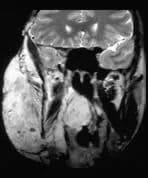

There is an enormous facial angioma extending through the palate to almost obliterate the oro-pharyngeal airway. A small extension into the middle cranial fossa from the infra temporal fossa is shown. Signal change is present in the immediately overlying brain suggesting a breach in the dura. Bone is partly destroyed in and around the right orbit, especially the right frontal bone.